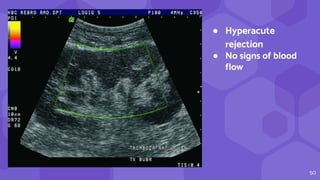

● Hyperacute

rejection

● No signs of blood

flow